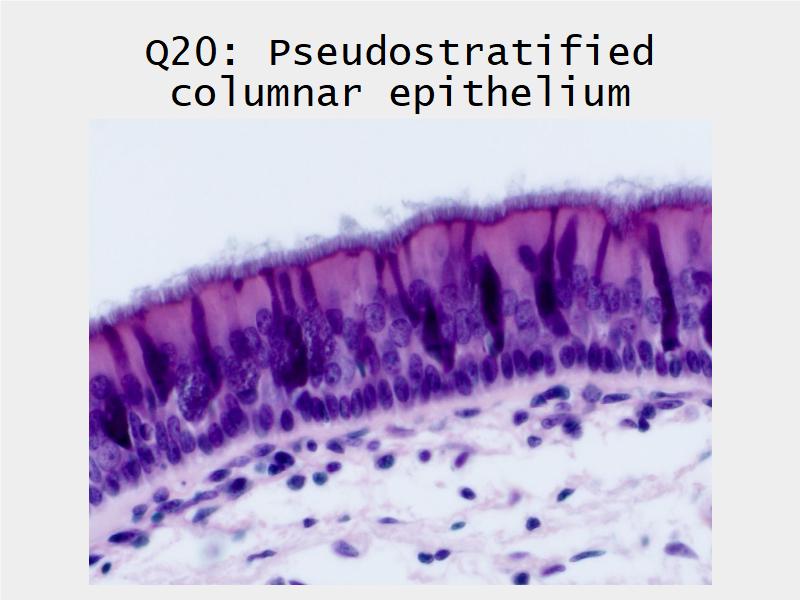

Respiratory epithelium

- Pseudostratified

- Ciliated

- Columnar

- Epithelium with

- 4 Cells

- Ciliated columnar cells

- Non-ciliated columnar cells

- Goblet cells

- Basal cells